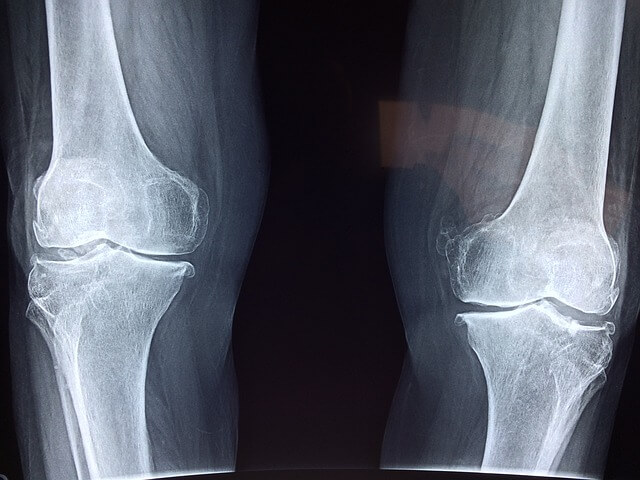

- 관절 통증 완화 : 콘드로이친은 관절의 윤활을 도와주어 통증을 줄이는 데 기여합니다. 특히 퇴행성 관절염 환자에게 효과적이라는 연구 결과가 있습니다.

- 연골 보호 : 콘드로이친은 연골의 구조를 유지하고 손상을 방지하는 데 도움을 줍니다. 이는 관절의 기능을 향상하고 노화로 인한 연골 손실을 늦추는 데 기여합니다.